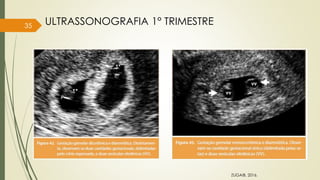

ZUGAIB, 2016.

ULTRASSONOGRAFIA 1° TRIMESTRE

36

DETERMINAÇÃO DA ZIGOZIDADE, CORIONICIDADE E AMNIONICIDADE

 SINAL DO T = Monocoriônica

Figura 20

Figura 21

37

 SINAL DO LAMBDA = Dicoriônica

Figura 23 Figura 24